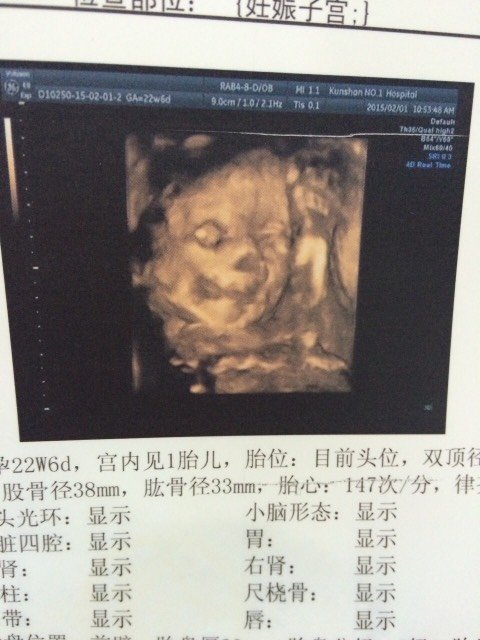

有没有专业人士解答,为什么我宝宝三维彩超的嘴巴边上那块是黑色的,是不是胎记呀,嘴巴和鼻子都看不清

你好,胎儿四维彩超是看不到胎儿脸上的胎记的,黑色的可能是其他的遮挡物造成的阴影,嘴巴和鼻子显示的不算很清晰,跟胎儿在宫内的姿势有关,只要B超大夫说没问题就行。